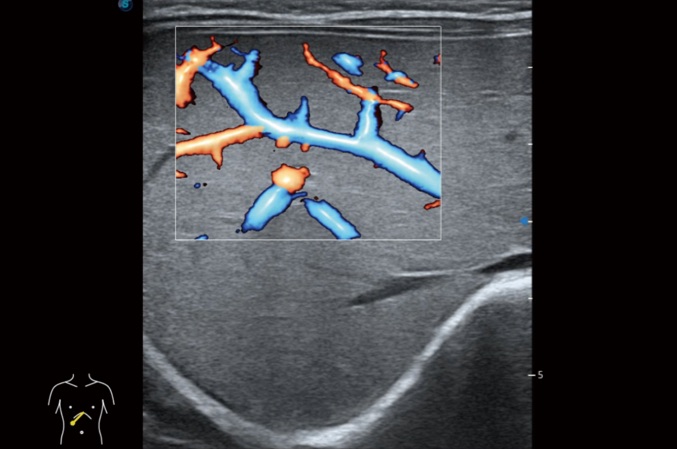

高分辨率血流成像技术提高了对低速血流信号的检测能力。在提高空间分辨率的同时,也克服了血流外溢现象,为用户提供更加真实的血流动力学信息。

小器官应用